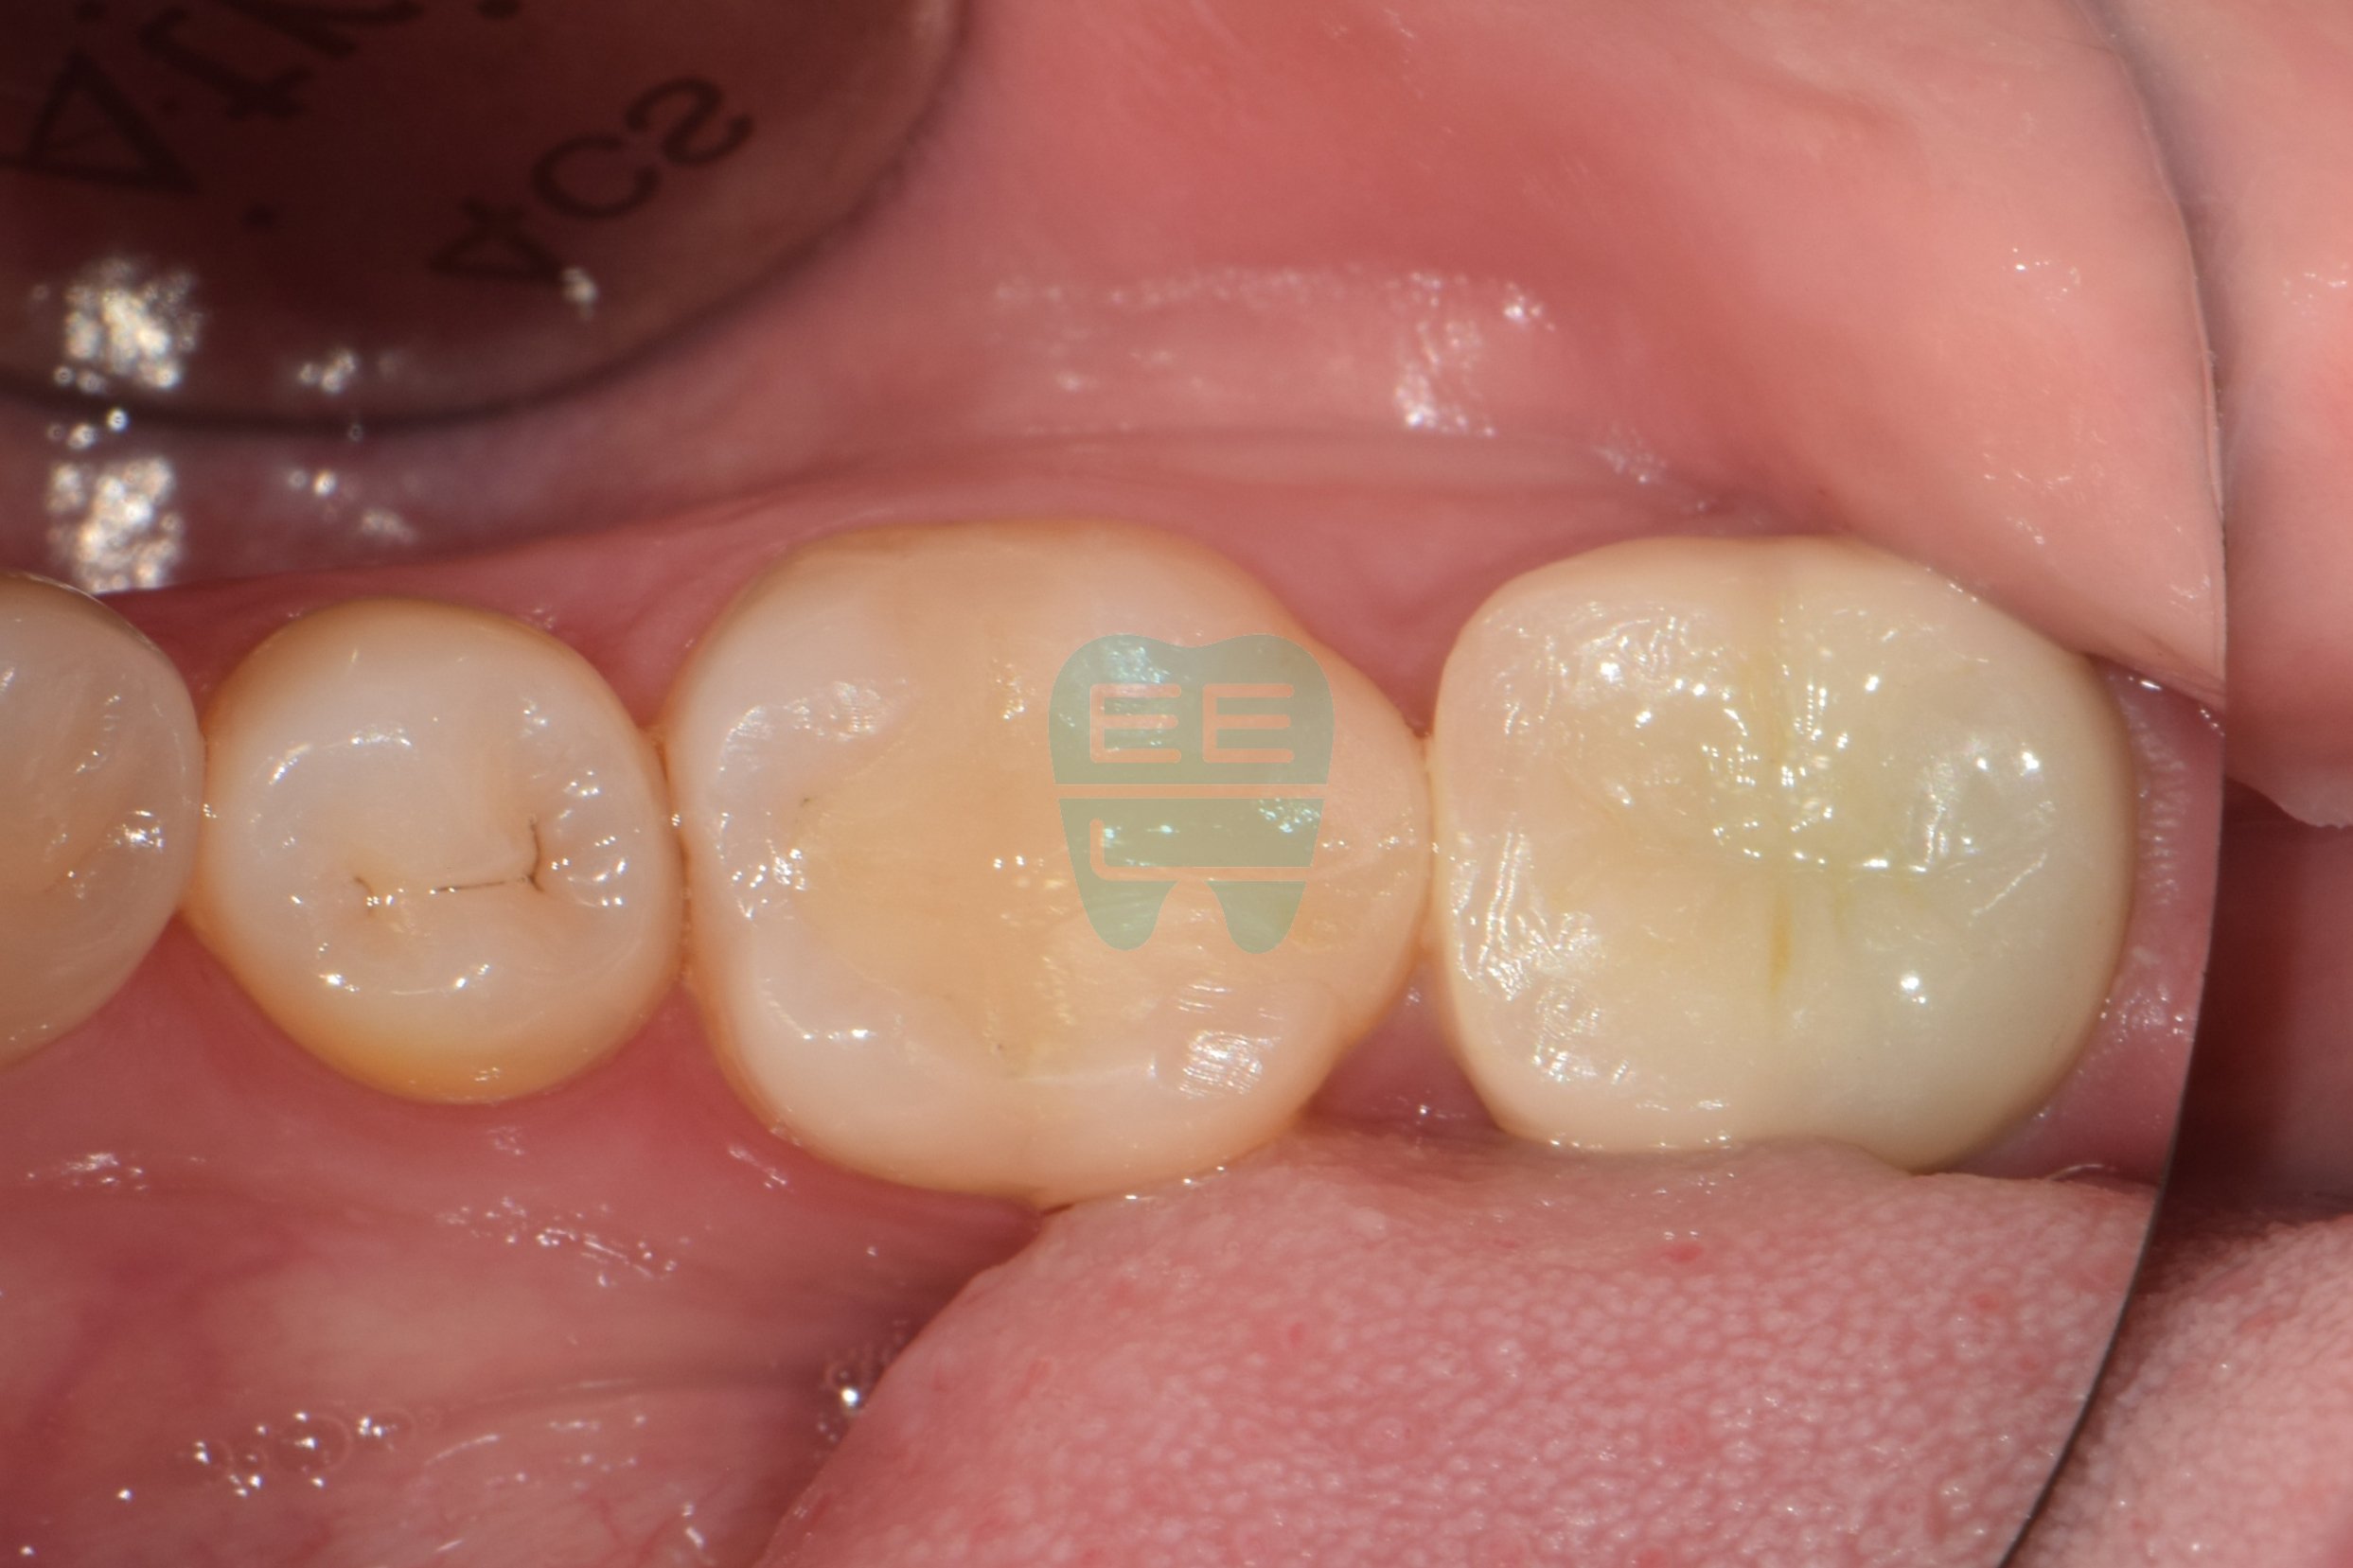

STEP 1. 치료 전 상태 확인

환자분은 1~2년 전 타 치과에서 사랑니로 인한 충치 치료를 위해 신경치료와 지르코니아 크라운 치료를 받으셨습니다. 그런데 최근 크라운 주변에서 불쾌한 냄새가 지속적으로 난다는 주소(Chief Complaint)로 내원하셨습니다.

겉으로 보기에는 크라운이 멀쩡하게 씌워져 있었지만, 냄새의 원인을 찾기 위해 크라운을 제거하기로 했습니다.